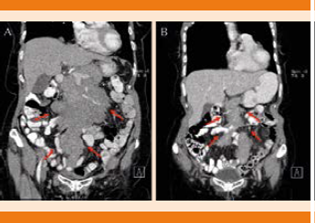

En noviembre de 2016 acudió nuevamente al servicio de urgencias por padecer astenia, adinamia, pérdida de peso y dolor en el epigastrio, de tipo urente, transfictivo. Se realizó un ultrasonido abdominal que reportó probable lesión hepática con infiltración a epiplón, los marcadores tumorales se reportaron alterados: Ca 125 en 579.3 ng/mL y Ca 19.9 en 87 U/mL. La tomografía abdominal con doble contraste mostró un tumor retroperitoneal y derrame pleural derecho de más de 50% del área pulmonar total. Fue valorada por el servicio de hematología donde se consideró la posibilidad de recaída del mieloma múltiple o una segunda neoplasia (Figuras 1 y 2).

Figura 1 A. Tumor retroperitoneal corte coronal, previo a quimioterapia. B. Tumor retroperitoneal corte coronal, con disminución del tamaño posterior a ciclo de quimioterapia.